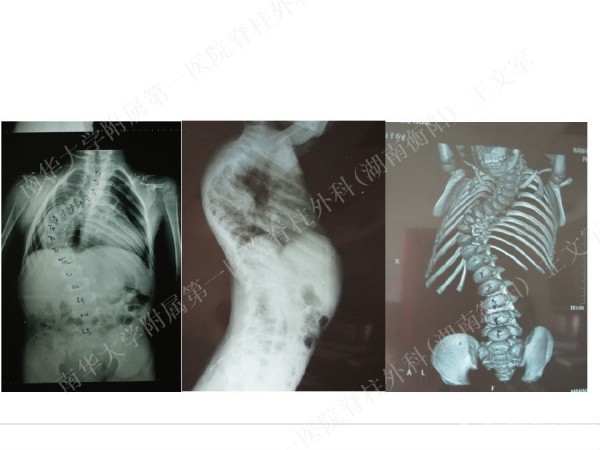

拥有完全自主知识产权的滑槽钉生长棒非融合技术,由南华大学附属第一医院脊柱外科王文军教授研发。

该技术在提供良好矫形固定效果的同时,保留了脊柱生长潜能、尽可能减少对患儿脊柱生长的影响,初步临床效果显示该系统是简单安全有效的,是严重儿童早发脊柱侧弯矫形治疗的一种有益尝试。

擅长脊柱脊髓疾病的微创及非融合手术治疗,目前率领科室开展的先进微创手术有:椎间孔镜技术、经皮穿刺腰椎外固定支架术治疗胸腰椎骨折、腹腔镜下人工腰椎间盘置换术、胸腔镜下胸椎前路手术、腰骶椎轴向融合术。率先在全国业界提出组合微创技术的理念,大大提升了脊柱微创技术的应用范围和治疗效果。拥有自主知识产权的生长棒技术在早发性脊柱侧弯术中的应用解决了儿童脊柱侧弯既早期矫形,又不影响生长发育的世界性难题。